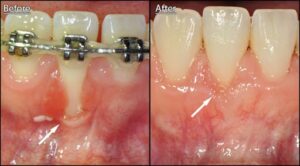

Potential Oral Health Challenges with Braces

The main concern with braces is that they can create additional nooks and crannies where food particles and plaque can accumulate, making it harder to keep teeth and gums clean. This increased risk of plaque buildup can potentially lead to gum disease if proper oral hygiene is not maintained.

If signs of gum disease appear during your orthodontic treatment, early intervention is key. Your periodontist may recommend a deep cleaning procedure known as scaling and root planing to remove tartar and bacteria from below the gum line.